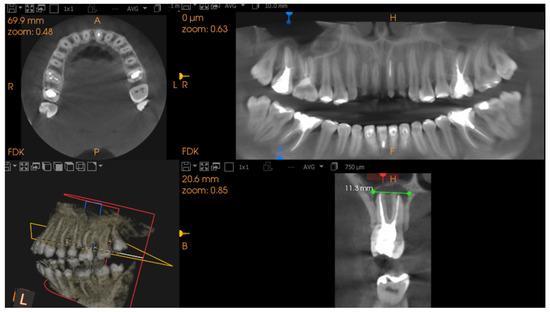

2.3. CBCT Imaging Parameters

- Correct root canal filling, the apical limit of the root canal filling at 0–0.5 mm from the radiological apex;